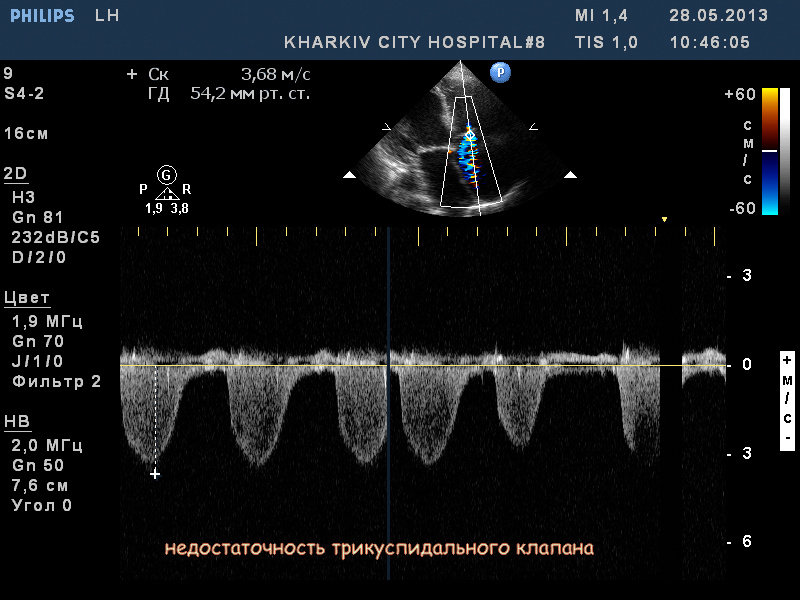

Пациентка 83 лет. Жалобы на сильную одышку в теч. последнего месяца.

В полости левого желудочка в базальном сегменте имеется образование с неровным контуром до 2.4см- вероятно миксома левого желудочка.

кальциноз створок АК, дилатация левого предсердия, правых полостей, выраженная недостаточность ТК и клапана ЛА, гипертрофия левого желудочка. Дополнительные косые хорды левого желудочка. Высокая ЛГ (АТ/ЕТ- 0.20 Рсред. ЛА-69мм рт.ст.).